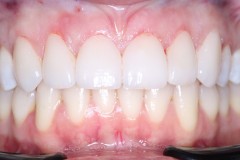

Caso 5

Se realizan Coronas dentales en Ziconio para mayor resistencia,mejorar armonia y estética, en piezas con resinas desajustadas y caries recidivas.